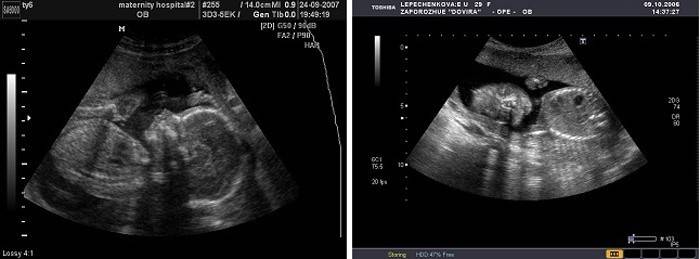

Exame de ultra-som (Uzi)

Normalmente, um exame de ultrassonografia de 20 semanas é agendado como parte de um segundo estudo de rastreamento. no contexto deste estudo, é possível confirmar o sexo do feto assumido na ultra-sonografia anterior, bem como avaliar muitos indicadores de desenvolvimento do bebê, identificar anormalidades do desenvolvimento e patologias genéticas. Neste período, é feita uma avaliação da altura e peso do feto, a sua conformidade com a idade gestacional, posição e condição da placenta, a quantidade de líquido amniótico. Com ultra-som, o médico estuda a estrutura dos rins, coração, intestinos do feto, bexiga, fígado e pulmões e cérebro. O coração fetal é estudado levando-se em conta o fluxo sanguíneo usando-se a dopplerometria e, se forem detectados defeitos cardíacos, medidas adicionais serão necessárias.

Nesse período, é possível realizar ultrassonografia 3D de acordo com as indicações especiais ou a pedido dos pais.